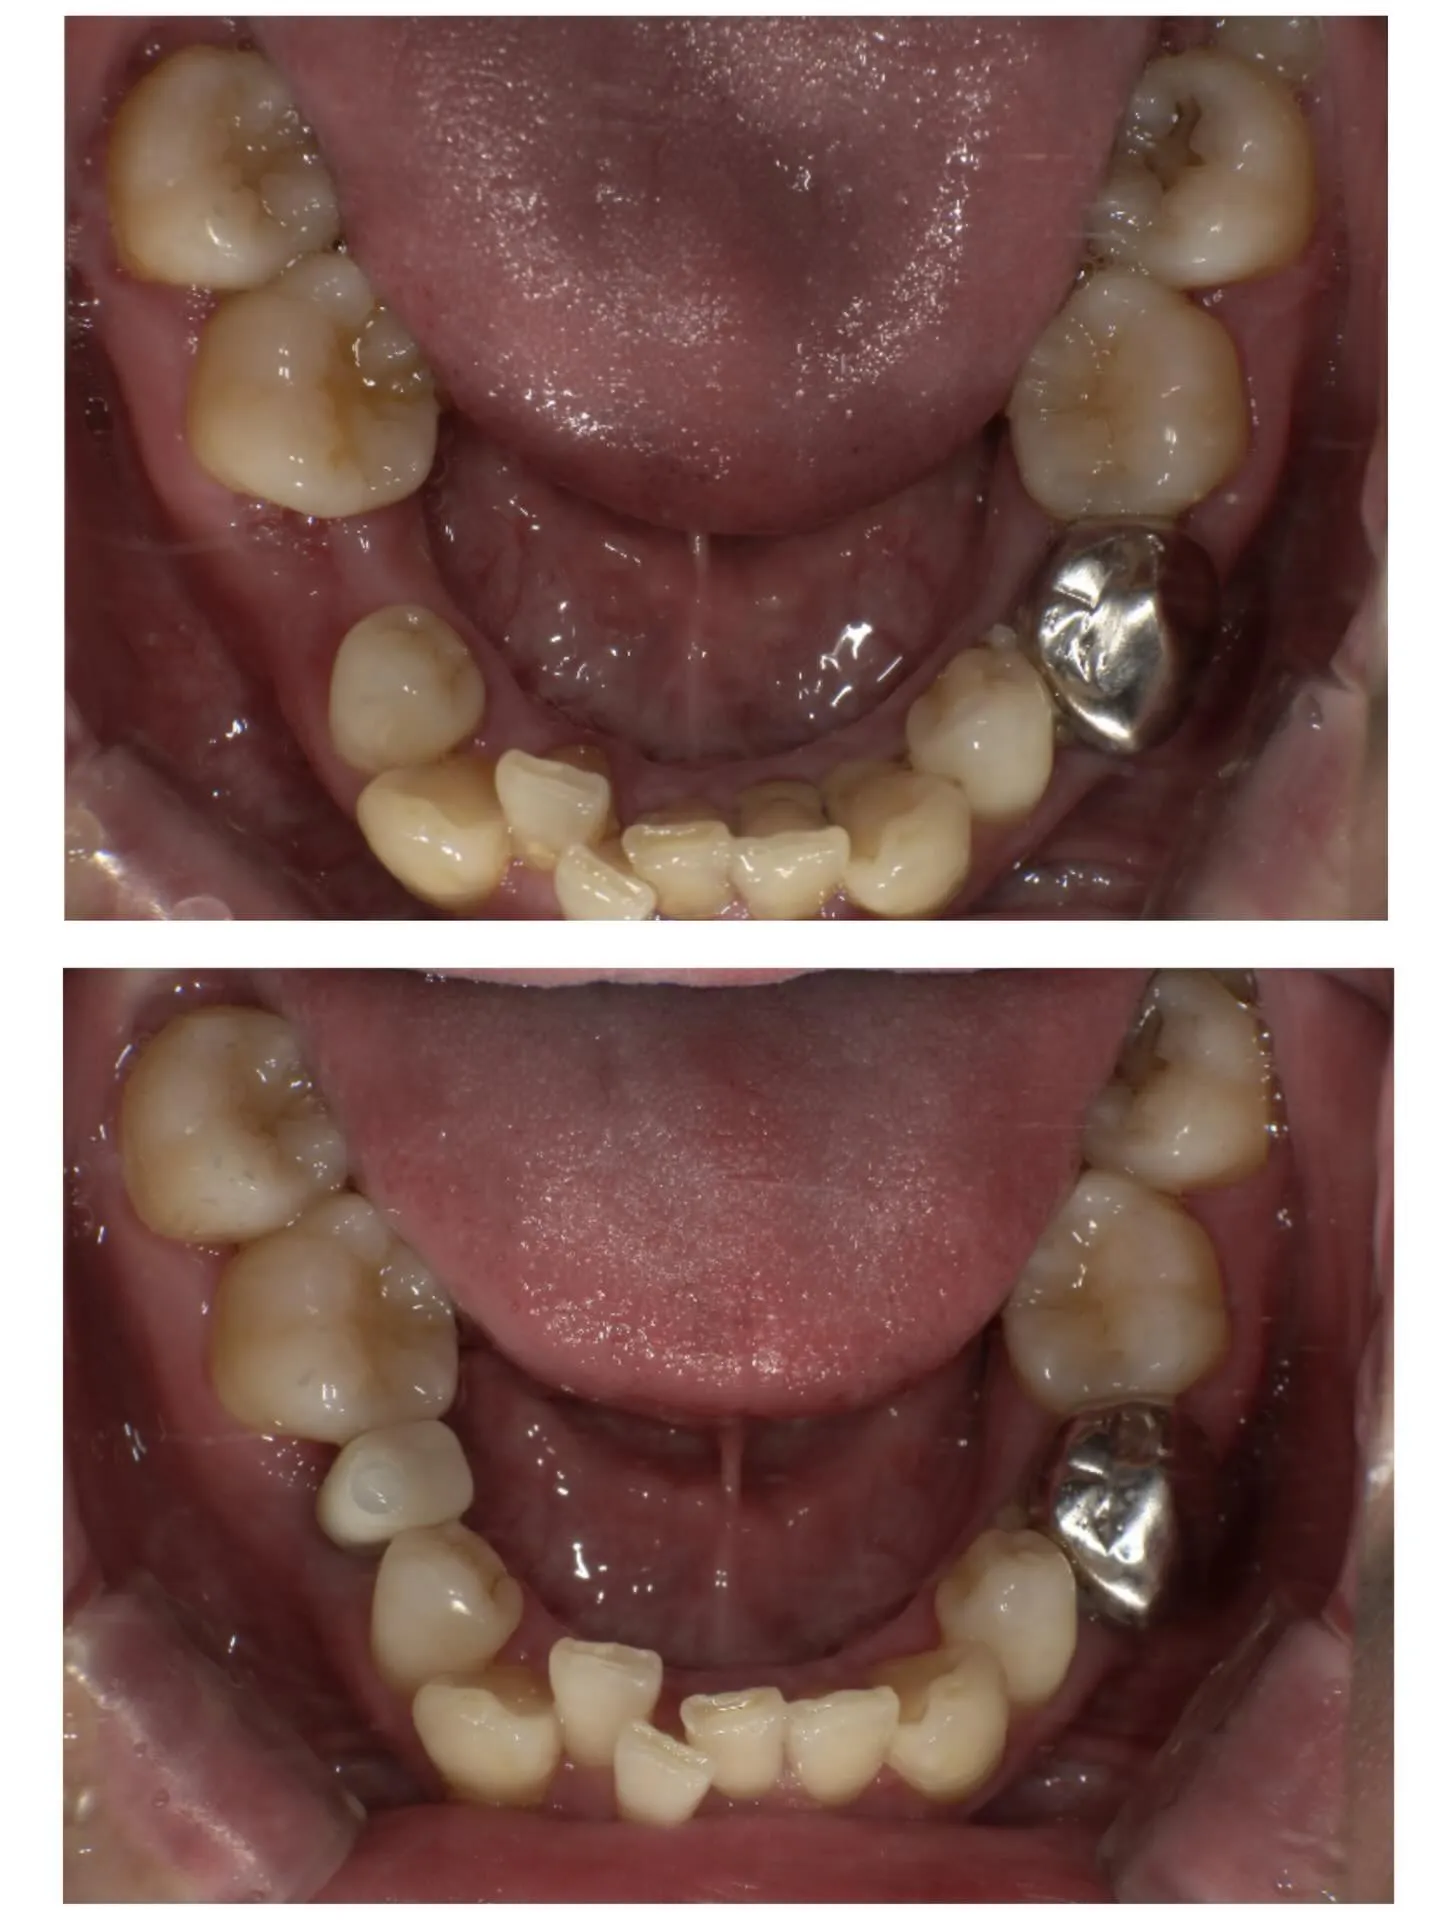

【インプラント症例】

右下の5番目の歯を失った部分に

インプラント治療を行い、

当日に被せ物までセットしました🦷